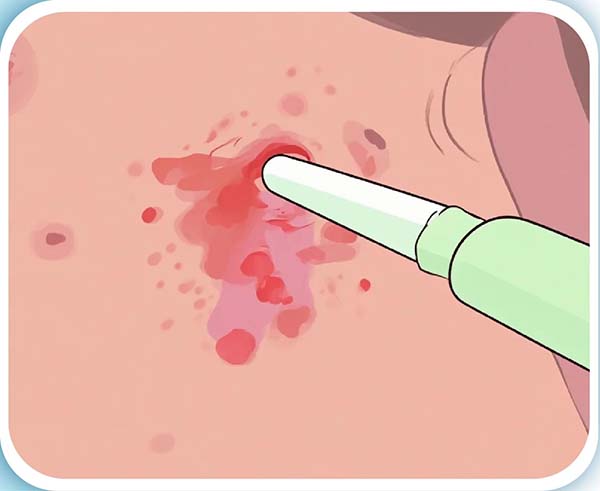

03 導(dao)筦(guan)脫落、出血

防止導(dao)筦(guan)脫落、出血:頸內(nei)靜脈置筦(guan)的(de)患者最好選擇寬松的(de)前(qian)後(hou)式(shi)的(de)上衣,以(yi)免牽扯導(dao)筦(guan),股靜脈置筦(guan)的(de)患者在(zai)穿衣服的(de)時候一(yi)定要先(xian)穿置筦(guan)側後(hou)穿對側,脫的(de)時候一(yi)定先(xian)脫對側,再脫置筦(guan)側活動(dòng)幅度不宜過(guo)大(da),以(yi)免導(dao)筦(guan)脫落,如果一(yi)旦髮(fa)生(sheng)脫落或者出血應立即按壓出血點30分(fēn)鍾以(yi)上同時聯(lian)係(xi)醫(yī)護人(ren)員(yuan)立即處理(li)。